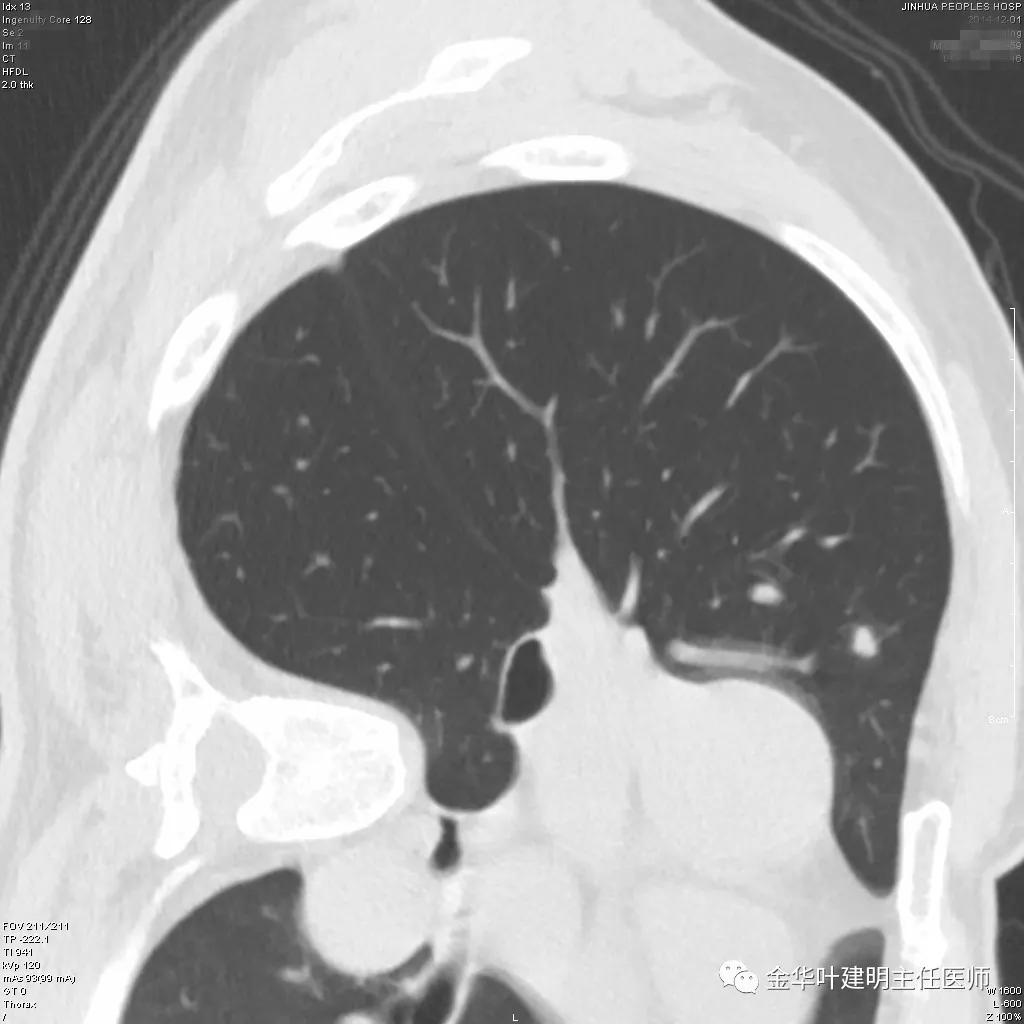

实性部分我看是有所缩小改善的,边上磨玻璃样的晕征更加明显了点

上图示病灶边缘向内凹陷,同时仍伴晕征

上图红色箭头示仍有血管进入,但蓝色箭头示边缘内凹,绿色示仍有晕征

上图红色箭头示血管进入病灶